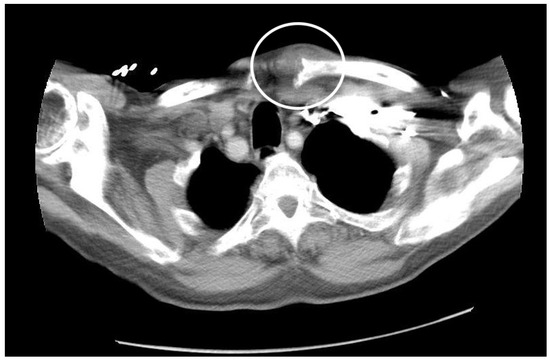

As it was believed that the E. coli bacteremia had seeded the SCJ, leading to septic arthritis, the ceftriaxone dose was increased to 2 g intravenous daily, and a computed tomography (CT) scan of the chest with contrast was obtained and showed widening of the left sternoclavicular joint and increased soft tissue fullness surrounding the joint, consistent with a septic joint. There was no fluid collection, or signs of osteomyelitis (Figure 2).

Figure 2.

CT scan of the chest with contrast.

The CT scan shows widening of the left sternoclavicular joint and increased soft tissue fullness surrounding the joint, consistent with septic joint.